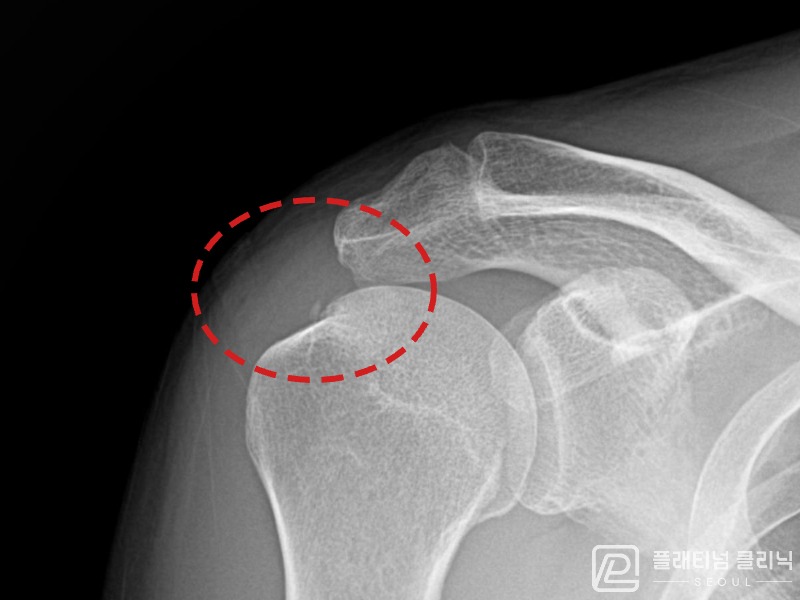

[촬영시기:21.09.02~21.10.07]

[석회분쇄흡입술] 좌측 어깨 통증으로 팔을 옆으로 올리기 어려워진 60대 남성 환자로, X-ray에서 좌측 극상근건 내 석회 침착이 확인되어 석회분쇄흡입술을 시행하였습니다.